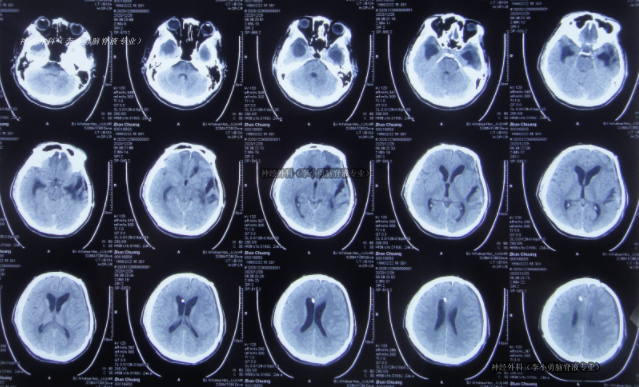

入院时:意识模糊,右上肢活动差,鼻饲、留置尿管。CT示颅骨缺损、脑积水、脑膨出。